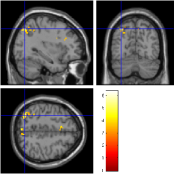

For the aC-aS contrast, Fig. 9 [top] shows, for the most significant slice and , that all pMRI reconstruction algorithms succeed in finding evoked activity in the left parietal and frontal cortices, more precisely in the inferior parietal lobule and middle frontal gyrus according to the AAL template666available in the xjView toolbox of SPM5.. Tab. 3 also confirms a bilateral activity pattern in parietal regions for . Moreover, for , Fig. 9 [bottom] illustrates that our pipeline (UWR-SENSE and 4D-UWR-SENSE) and especially the proposed 4D-UWR-SENSE scheme enables to retrieve reliable frontal activity elicited by mental calculation, which is lost by the the mSENSE algorithm. From a quantitative viewpoint, the proposed 4D-UWR-SENSE algorithm finds larger clusters whose local maxima are more significant than the ones obtained using mSENSE and UWR-SENSE, as reported in Tab. 3. Concerning the most significant cluster for , the peak positions remain stable whatever the reconstruction algorithm. However, examining their significance level, one can first measure the benefits of wavelet-based regularization when comparing UWR-SENSE with mSENSE results and then additional positive effects of temporal regularization and 3D wavelet decomposition when looking at the 4D-UWR-SENSE results. These benefits are also demonstrated for .

| mSENSE | UWR-SENSE | 4D-UWR-SENSE | |

|---|---|---|---|

|

|

|

|

|

|

|

| cluster-level | voxel-level | |||||

| p-value | Size | p-value | T-score | Position | ||

| mSENSE | 320 | 6.40 | -32 -76 45 | |||

| 163 | 5.96 | -4 -70 54 | ||||

| 121 | 6.34 | 34 -74 39 | ||||

| 94 | 6.83 | -38 4 24 | ||||

| UWR-SENSE | 407 | 6.59 | -32 -76 45 | |||

| 164 | 5.69 | -6 -70 54 | ||||

| 159 | 5.84 | 32 -70 39 | ||||

| 155 | 6.87 | -44 4 24 | ||||

| 4D-UWR-SENSE | 454 | 6.54 | -32 -76 45 | |||

| 199 | 5.43 | -6 26 21 | ||||

| 183 | 5.89 | 32 -70 39 | ||||

| 170 | 6.90 | -44 4 24 | ||||

| mSENSE | 58 | 0.028 | 5.16 | -30 -72 48 | ||

| UWR-SENSE | 94 | 0.003 | 5.91 | -32 -70 48 | ||

| 60 | 0.044 | 4.42 | -6 -72 54 | |||

| 4D-UWR-SENSE | 152 | 6.36 | -32 -70 48 | |||

| 36 | 0.009 | 5.01 | -4 -78 48 | |||

| 29 | 0.004 | 5.30 | -34 6 27 | |||